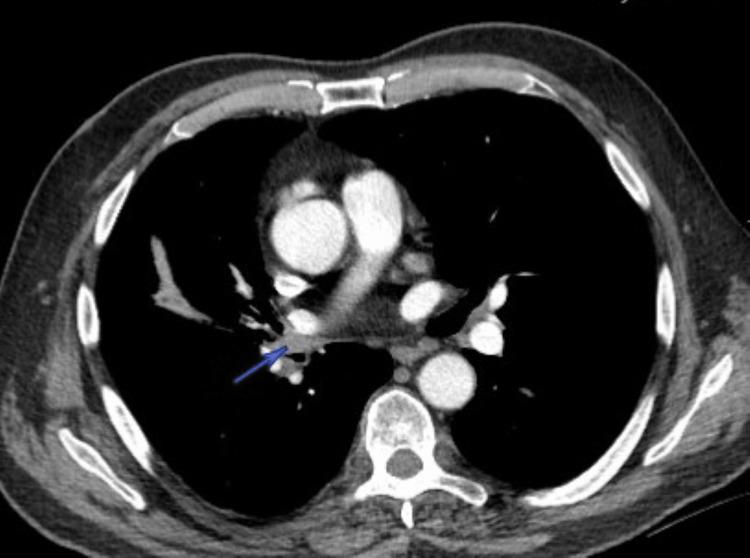

Pulmonary artery pseudoaneurysm (PAP) is a rare and potentially life-threatening vascular abnormality that is commonly associated with infections, such as tuberculosis. However, their occurrence in the setting of lung adenocarcinoma is exceedingly rare. We report a case of a 67-year-old man with stage III non-small cell lung cancer (NSCLC) who had a pulmonary artery pseudoaneurysm incidentally detected on follow-up maintenance imaging. The pseudoaneurysm was contiguous with pulmonary artery branches in the right lower lobe and associated with a progressively enlarging necrotic tumor region, suggesting that vascular invasion contributed to its formation. The patient was not experiencing any complications or hemoptysis at the time of identification; however, the pseudoaneurysm was deemed at risk for rupture and was successfully treated with coil embolization. This case highlights the importance of closely monitoring for vascular abnormalities in malignancy and early intervention to prevent potentially fatal complications.

肺动脉假性动脉瘤(PAP)是一种罕见且可能危及生命的血管异常,通常与感染有关,如肺结核。然而,它们在肺腺癌患者中极为罕见。我们报告一例67岁的III期非小细胞肺癌(NSCLC)男性患者,其在随访维持成像时偶然发现肺动脉假性动脉瘤。该假性动脉瘤与右下叶肺动脉分支相邻,并与逐渐增大的坏死肿瘤区域相关,提示血管侵犯促成了其形成。在发现时患者未出现任何并发症或咯血;然而,该假性动脉瘤被认为有破裂风险,并成功接受了弹簧圈栓塞治疗。该病例强调了在恶性肿瘤中密切监测血管异常以及早期干预以预防潜在致命并发症的重要性。